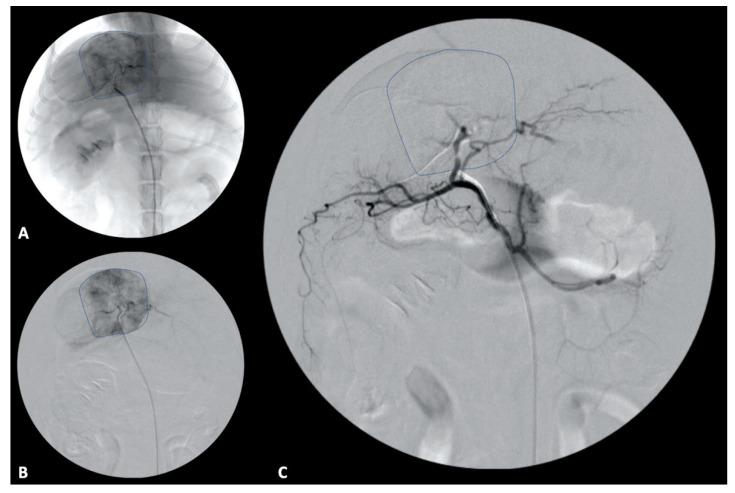

Primary hepatic neoplasia is uncommonly reported in dogs. Hepatocellular carcinoma (HCC) is the most frequent neoplasia identified in dogs and considerable effort has been committed towards identifying definitive and palliative treatment options. HCC is well recognized in humans as a sequelae of liver disease such as hepatitis or cirrhosis, while in dogs a similar link has failed to be fully elucidated. Management of HCC in people may be curative or palliative dependent on staging and transplant eligibility. Despite differences in etiology, there is substantial similarity between treatment options for liver neoplasia in human and veterinary medicine. The below summary provides a comparative discussion regarding hepatic neoplasia in dogs and people with a specific focus on HCC. Diagnosis as well as descriptions of the myriad treatment options will be reviewed.

原发性肝肿瘤在犬类中报道较少。肝细胞癌(HCC)是犬类中最常见的肿瘤,人们已付出相当大的努力来确定确定性和姑息性治疗方案。HCC在人类中被公认为是肝炎或肝硬化等肝脏疾病的后遗症,而在犬类中,类似的联系尚未完全阐明。人类HCC的治疗可能是治愈性的或姑息性的,这取决于分期和移植资格。尽管病因不同,但人类和兽医学中肝脏肿瘤的治疗选择有很大的相似性。以下总结对犬类和人类的肝肿瘤进行了比较讨论,特别关注HCC。将对诊断以及众多治疗选择进行综述。